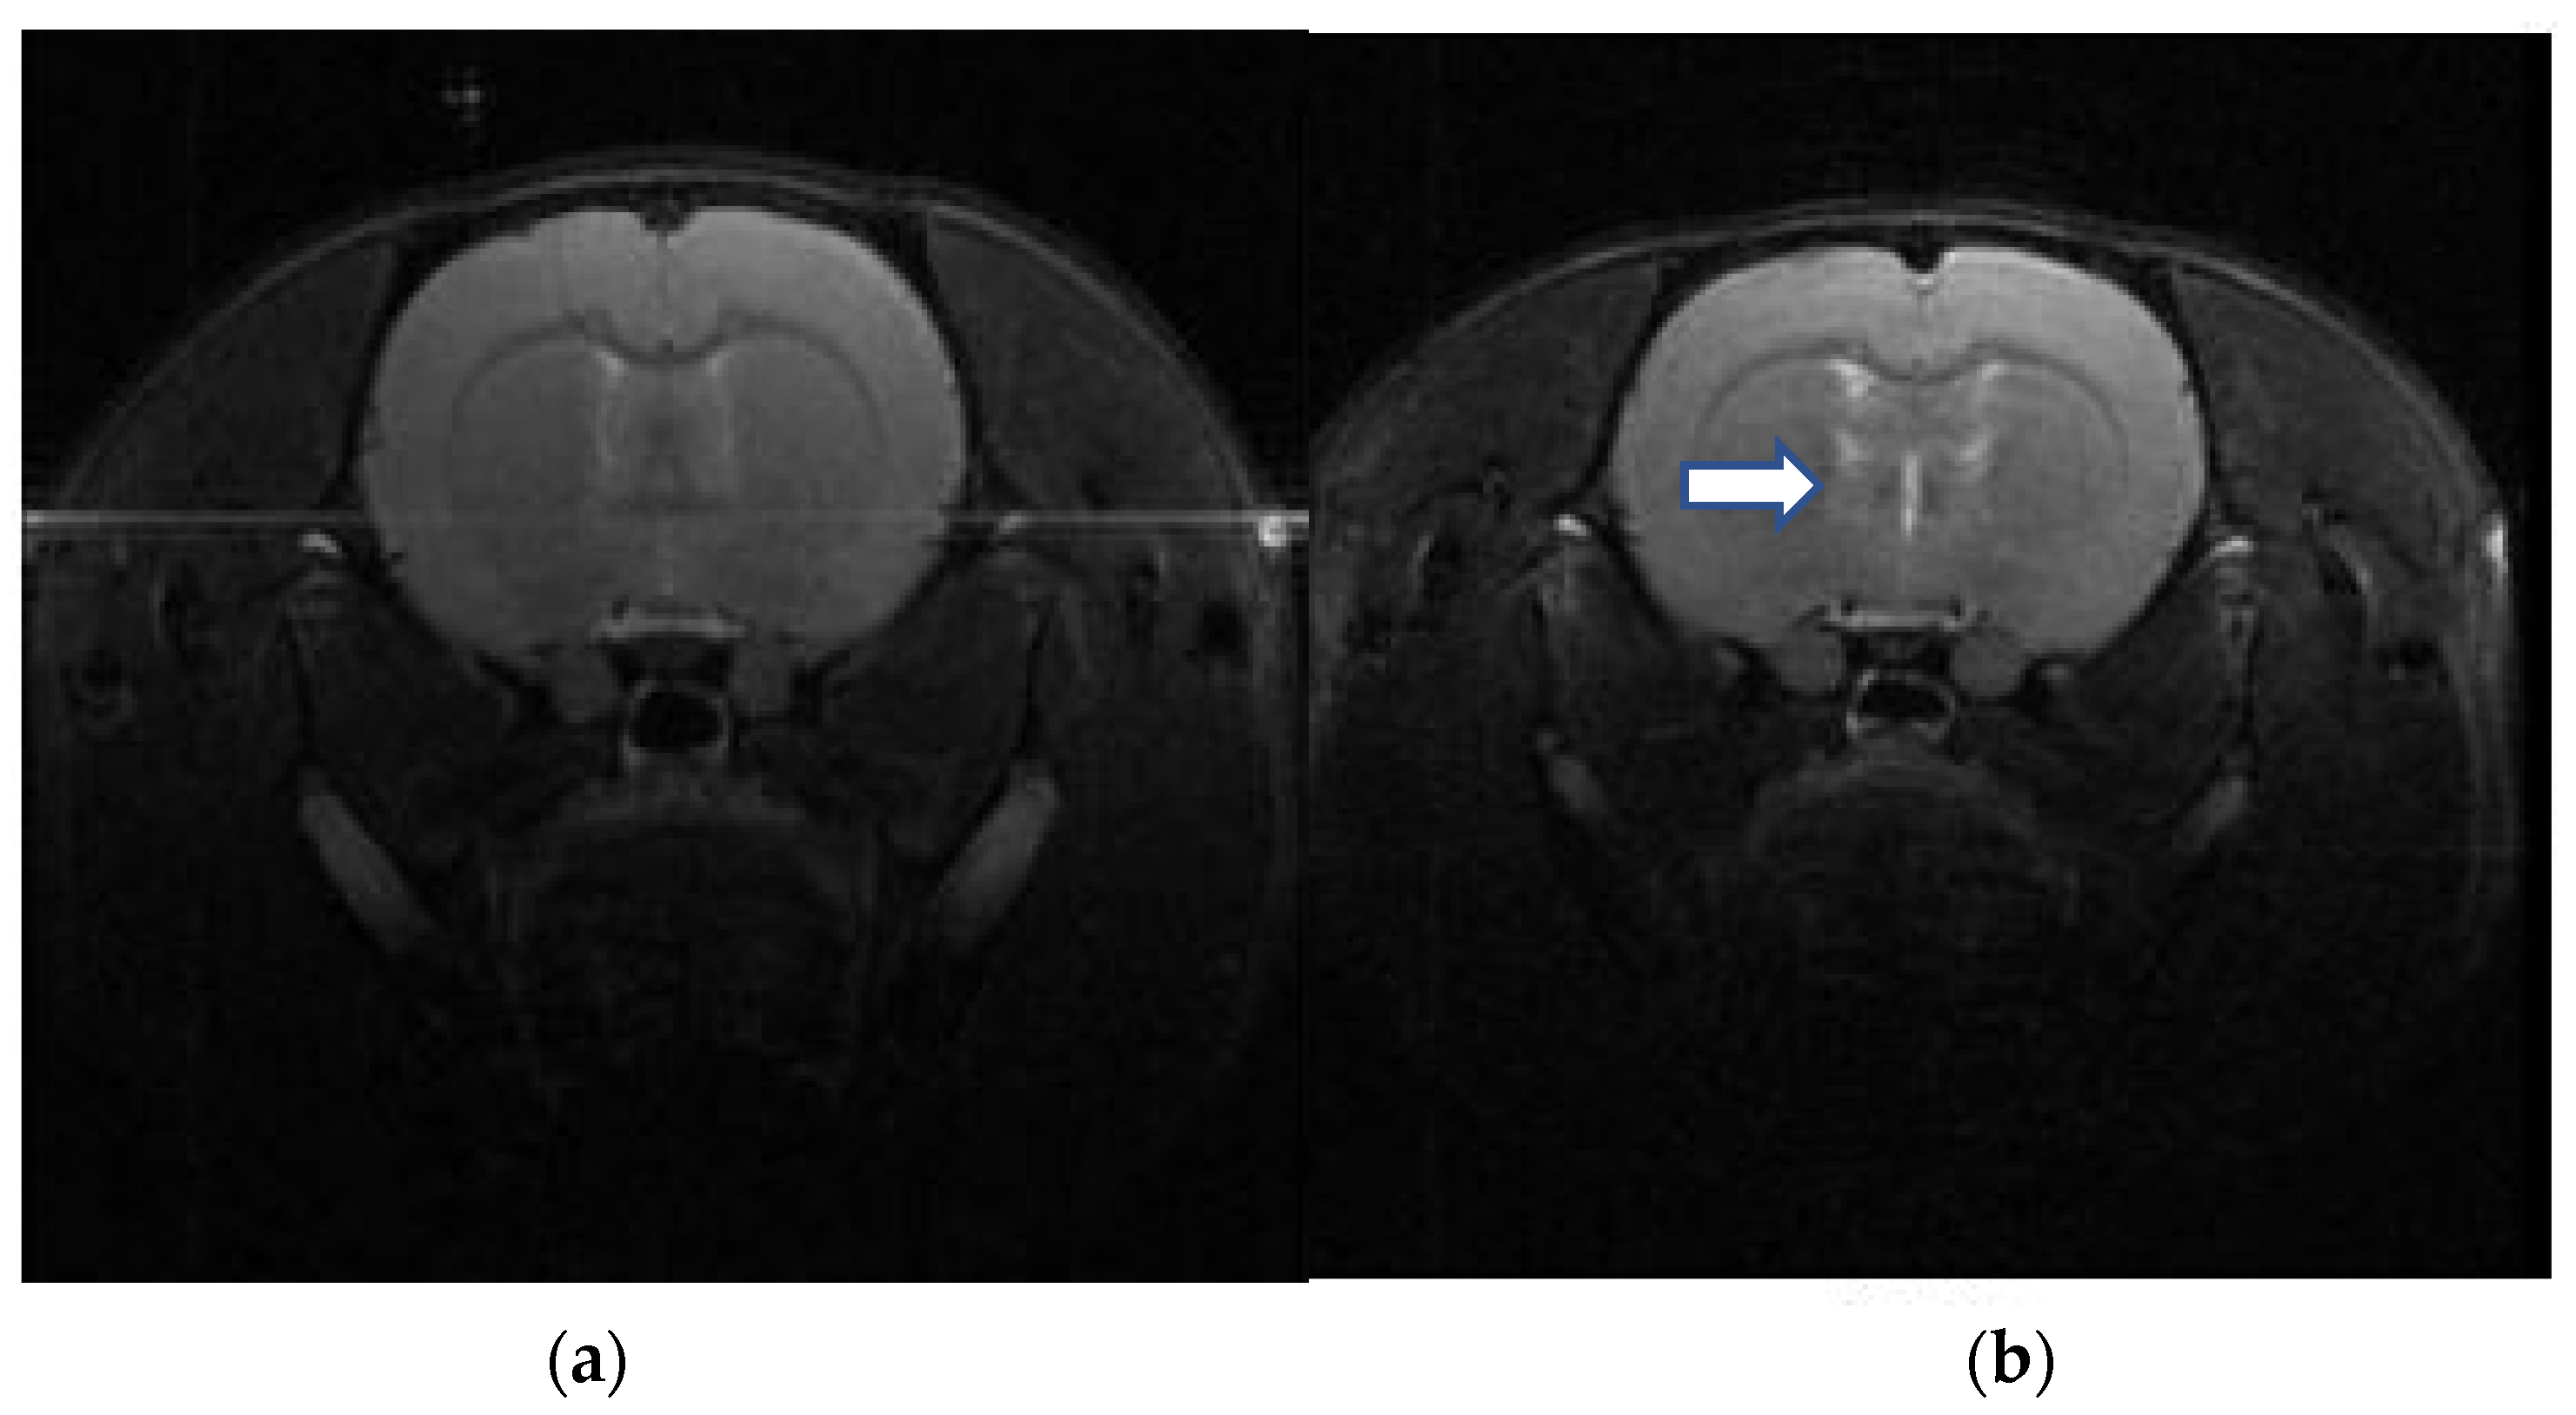

4.1. Imaging Study for DAI

- Frank, D.; Gruenbaum, B.F.; Zvenigorodsky, V.; Shelef, I.; Oleshko, A.; Matalon, F.; Tsafarov, B.; Zlotnik, A.; Frenkel, A.; Boyko, M. Establishing a 3-Tesla Magnetic Resonance Imaging Method for Assessing Diffuse Axonal Brain Injury in Rats. Int. J. Mol. Sci. 2024, 25, 4234. [Google Scholar] [CrossRef] [PubMed]